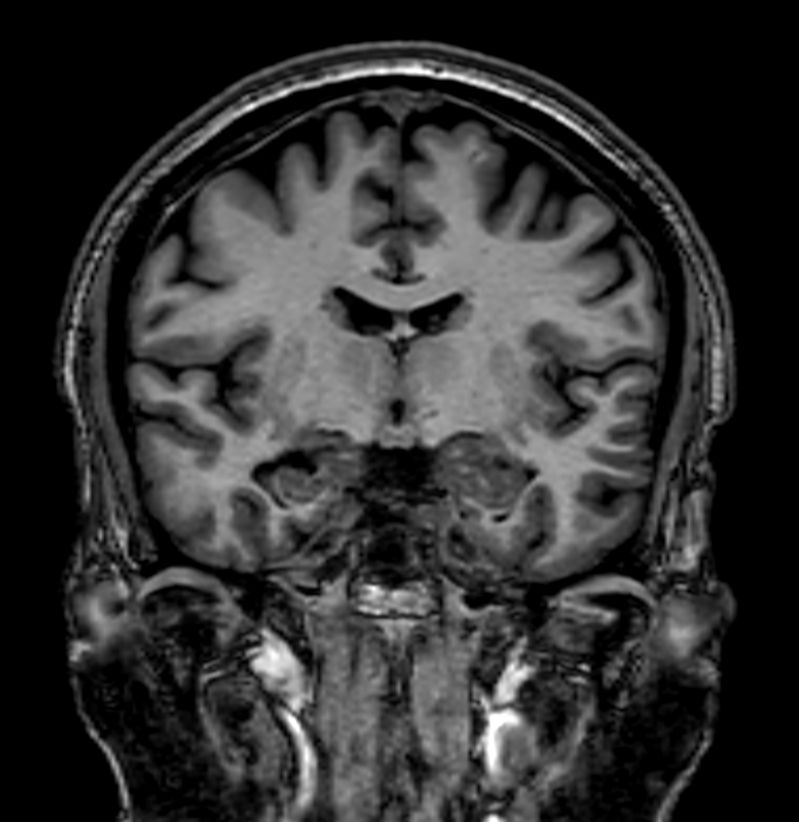

T2w TSE MultiVane XD